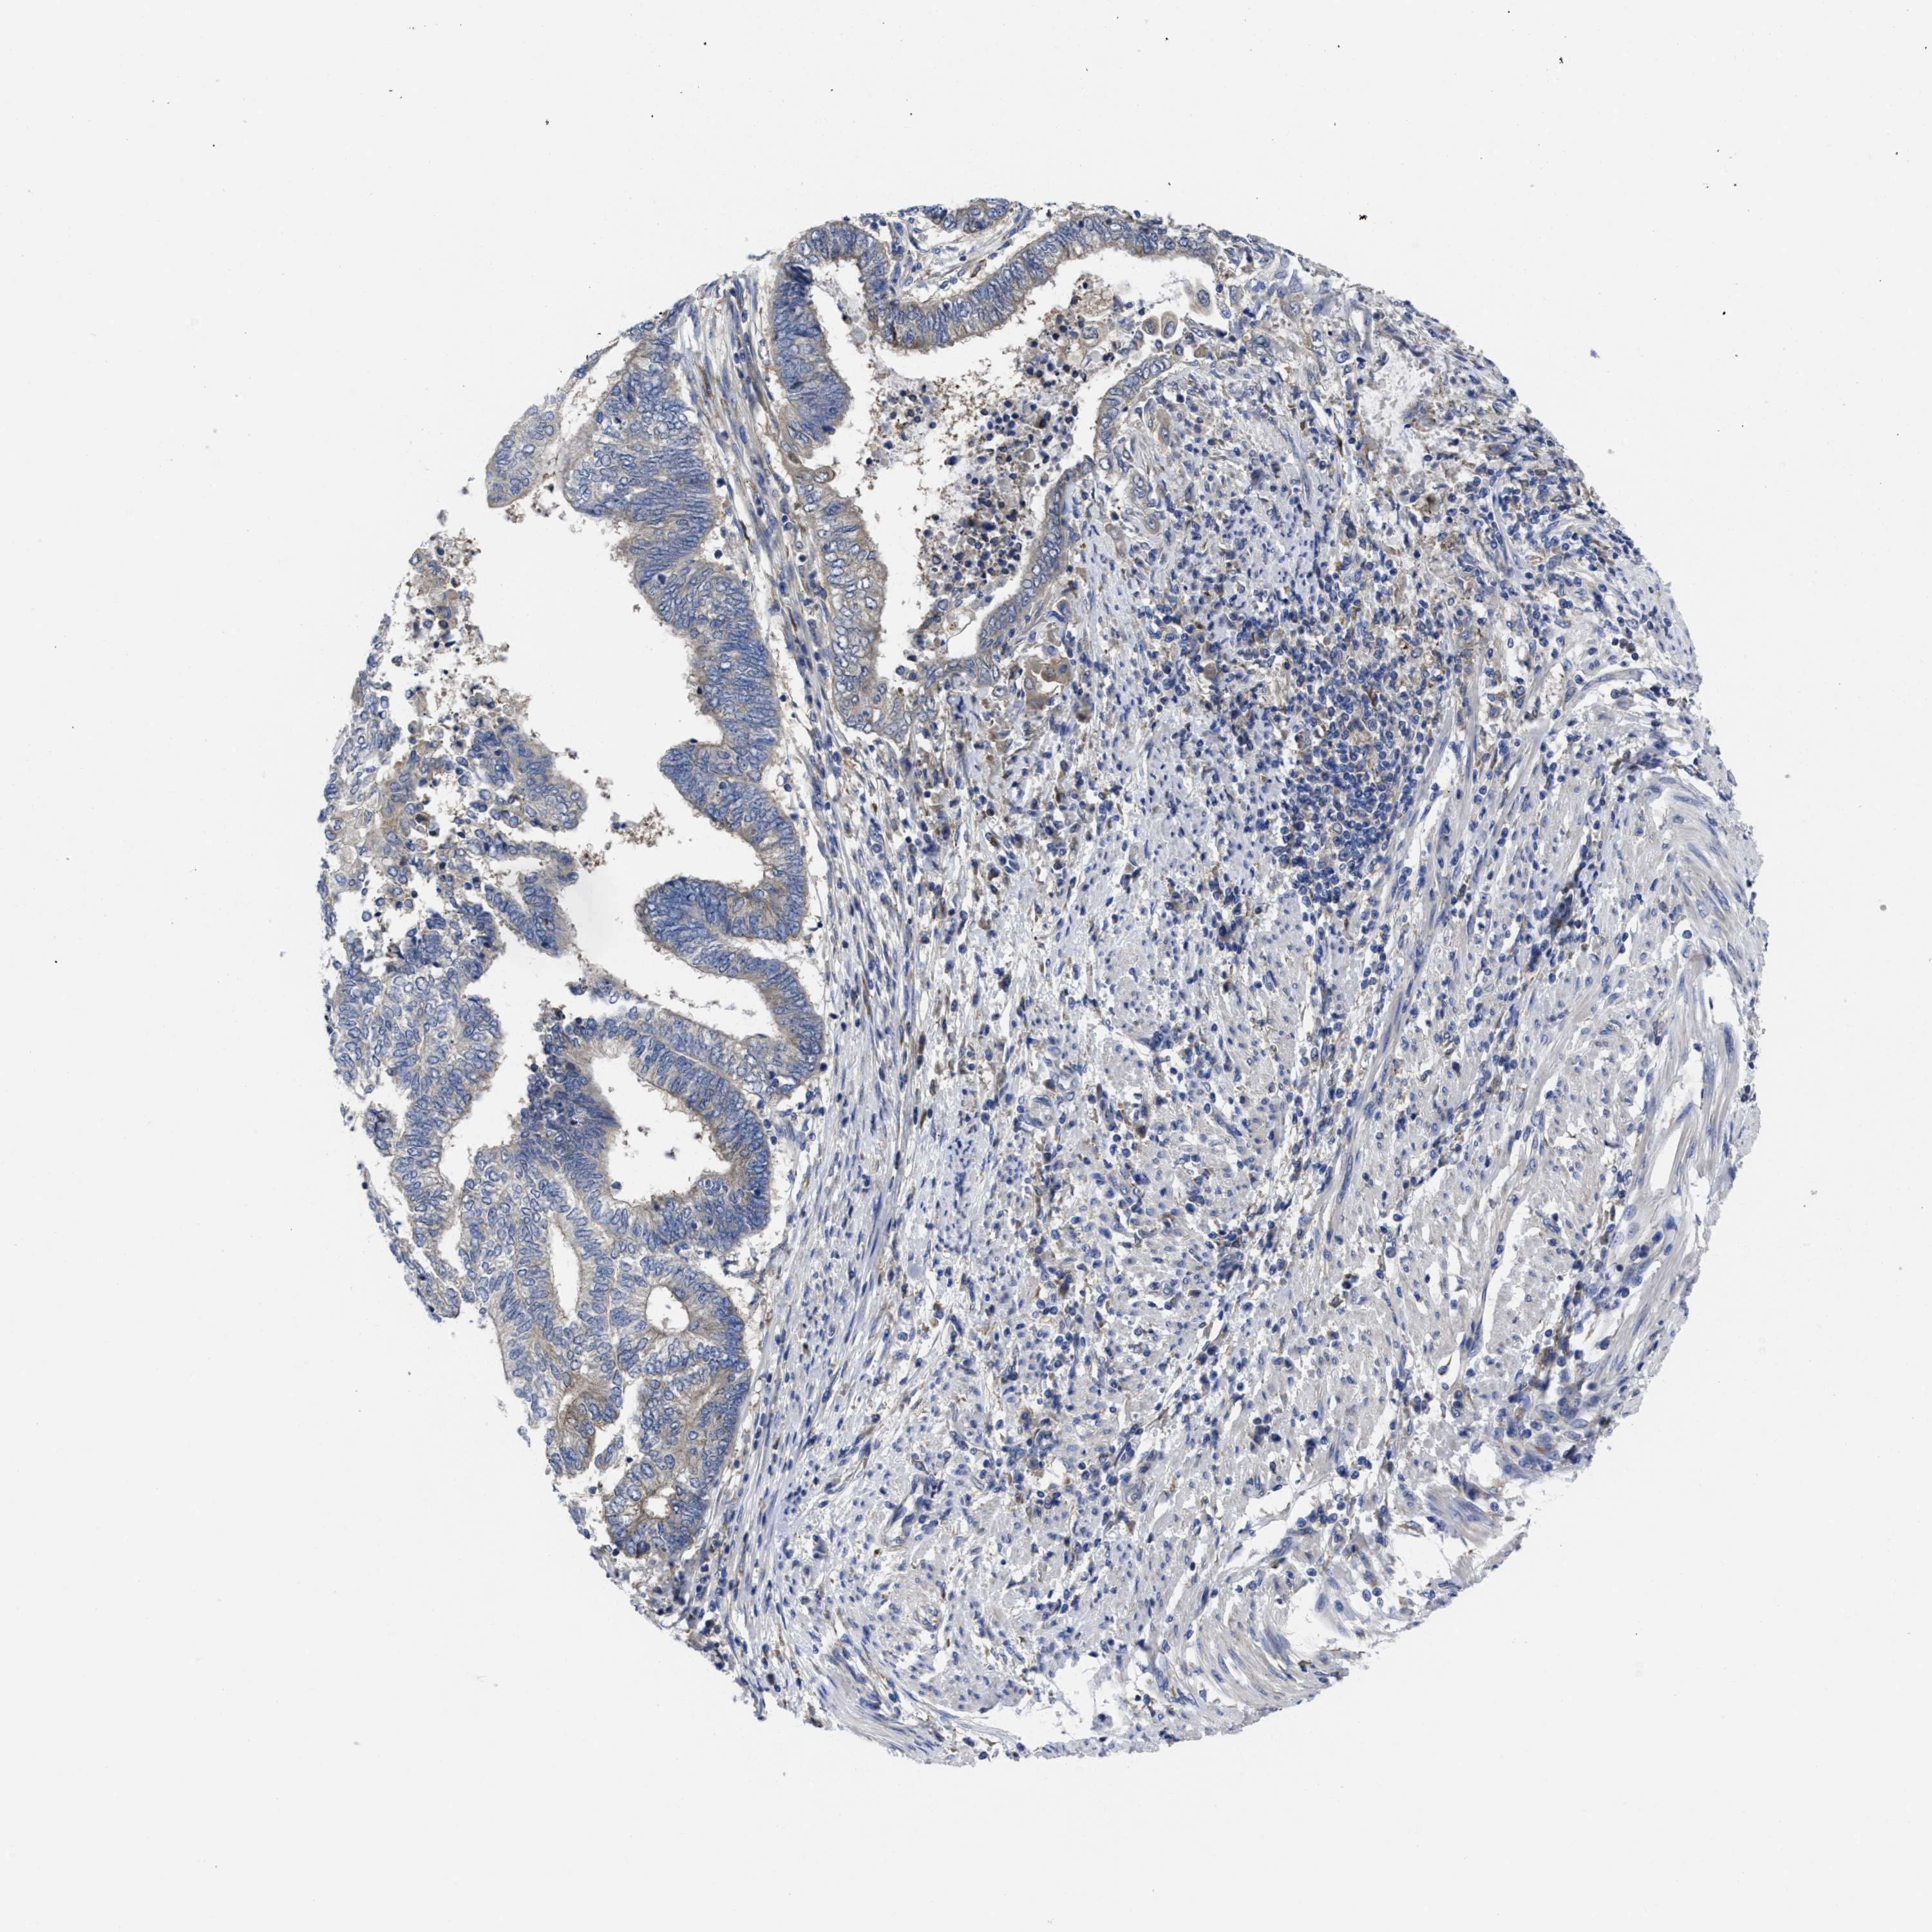

ENDOMETRIAL CANCER - Protein expressioni

A mouse-over function shows sample information and annotation data. Click on an image to view it in a full screen mode. Samples can be filtered based on level of antibody staining by selecting one or several of the following categories: high, medium, low and not detected. The assay and annotation is described here.

Note that samples used for immunohistochemistry by the Human Protein Atlas do not correspond to samples in the TCGA dataset.

Antibody stainingi

Antibody staining in the annotated cell types in the current human tissue is reported as not detected, low, medium, or high, based on conventional immunohistochemistry profiling in selected tissues. This score is based on the combination of the staining intensity and fraction of stained cells.

Each image is clickable and will lead to virtual microscopy that enables deeper exploration of all samples and also displays staining intensity scores, fraction scores and subcellular localization as well as patient and tissue information for each sample.

Antibody HPA022931

Staining

High

Medium

Low

Not detected

Intensity

Strong

Moderate

Weak

Negative

Quantity

>75%

75%-25%

<25%

None

Location

Nuclear

Cytoplasmic/membranous

Cytoplasmic/membranous,nuclear

Adenocarcinoma, NOS

Adenoma, NOS